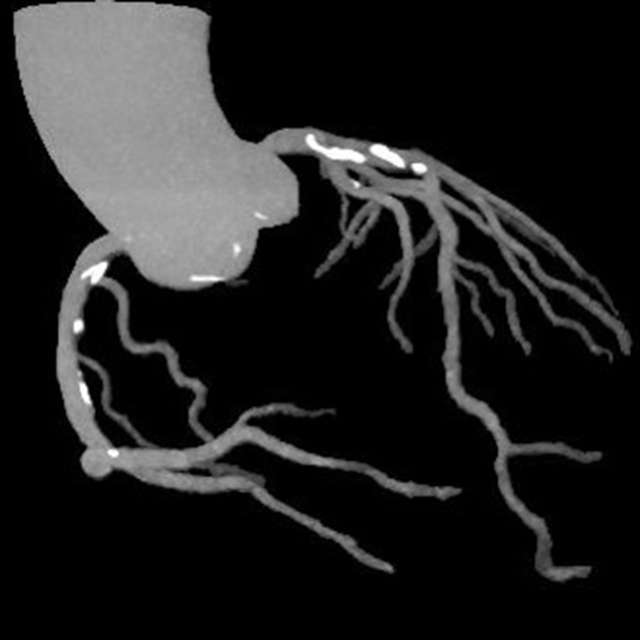

术后检查

这个真实案例强调了胸痛的凶险性、致命性以及一站式CT检查在及时诊断和治疗方面的不可或缺性。

2.主动脉夹层的检测:这一检查能够清楚地显示主动脉的解剖结构,帮助医生观察主动脉夹层并确定其位置和严重程度,及时进行干预。

3.肺栓塞的评估:通过一站式CT检查,医生可以识别肺栓塞并评估其大小以及位置,以指导治疗决策。